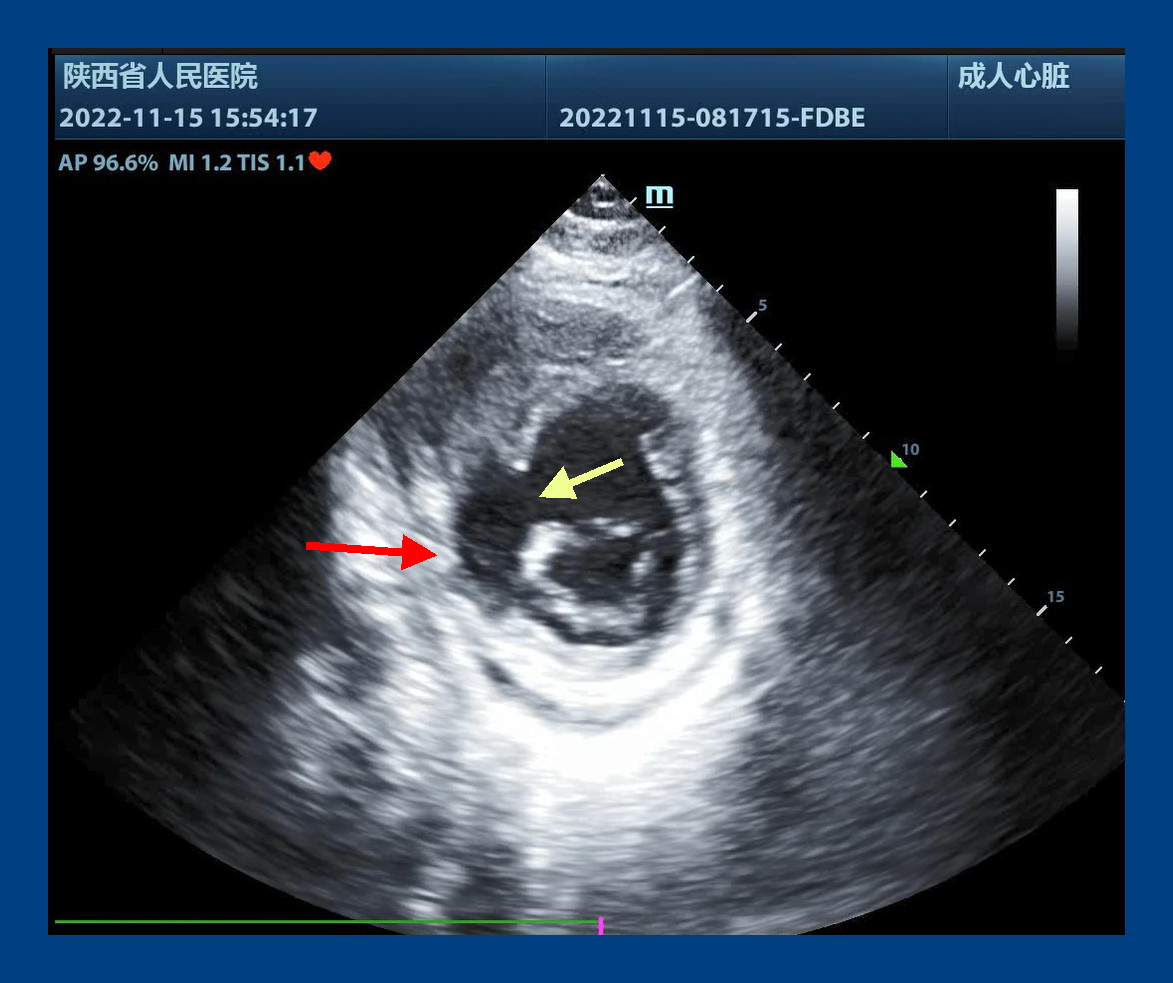

心脏外科,付建莉主任医师心脏超声检查,确诊为心脏左室下壁瘤样膨出,与正常室壁呈矛盾运动,测其瘤口为41mm,瘤深27mm,后室间隔下壁回声失落,左室面缺损口大小38mm,右室面缺损口大小21mm,病情十分危急。

心包切开后,发现大量血性心包积液,室壁瘤已经发生破裂,心脏严重水肿,经室壁瘤切口探查,发现一个近30毫米的巨大室间隔穿孔。术后经食道超声证实,室间隔穿孔消失,左心室前侧壁和下壁活动度改善,瓣膜未见反流。手术顺利结束,患者安全回到心外科ICU。